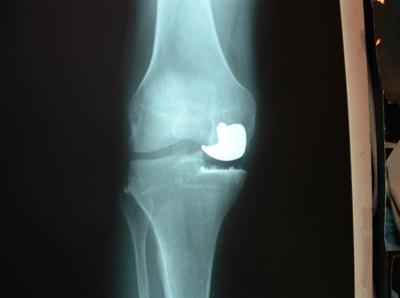

Uni-compartmental knee replacement. Only the medial compartment has been replaced

Arthritis of the knee should first be treated conservatively with anti-inflammatory medications, physical therapy, injections of steroids, injections of hyaluronic acid (Synvisc™, Hyalgan™, Supartz™), or arthroscopic surgery.  Traditional surgery, known as total knee replacement (TKR) replaces all three compartments of the knee.  The latest techniques allow selective replacement of each specific compartment.  This is called uni-compartmental replacement.  Another technique is MIS (minimally invasive surgery) a technique for decreasing post-operative pain and speeding recovery time.